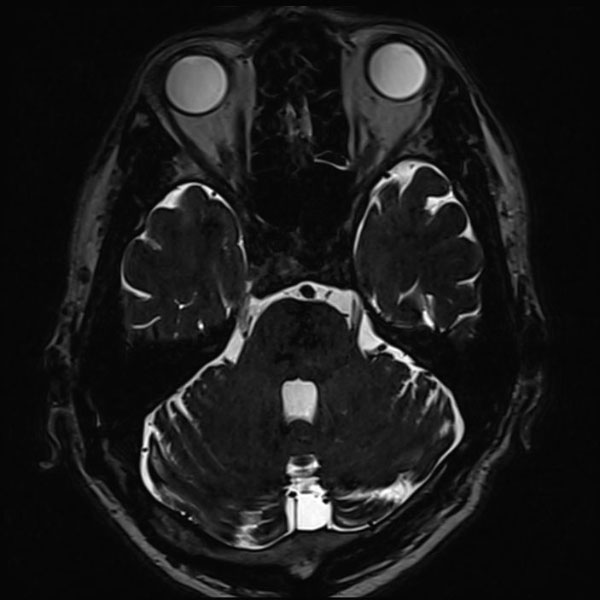

手術前

(MR1)